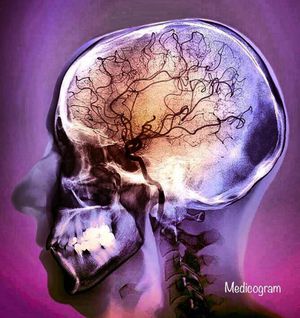

There are fewer blood vessels visible compared to normal. This is due to a blocked middle cerebral artery causing areas of ischaemia to parts of the brain. Strokes can be instantly fatal, or may pass unnoticed. Symptoms can include muscle weakness, behavioural changes or paralysis. The symptoms of stroke are distinct because they happen quickly: Sudden numbness or weakness of the face, arm, or leg (especially on one side of the body) Sudden confusion, trouble speaking or understanding speech Sudden trouble seeing in one or both eyes Sudden trouble walking, dizziness, loss of balance or coordination Sudden severe headache with no known cause So what to do if maybe your parents or relatives or friends look weird and absent? Act quickly. Why is there a need to act? Ischemic strokes, the most common type of strokes, can be treated with a drug called t-PA, that dissolves blood clots obstructing blood flow to the brain. The window of opportunity to start treating stroke patients is three hours, but to be evaluated and receive treatment, patients need to get to the hospital within 60 minutes. 📷•Medicogram•